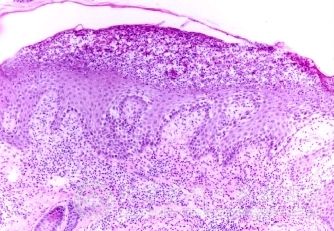

长期大量外用激素类药膏的后果有什么?目前,有很多人患有皮肤病,很多患者问这个皮肤病的问题,皮肤病给人们的生活工作带来了严重的影响。并且皮肤病比较顽固,让人们非常烦恼,皮肤病不仅给人们的身体造成了一定的影响,而且皮肤病还伴有各种不良症状,为了您能够尽快脱离皮肤病,恢复健康,同时避免加重皮肤病症状,同时加强对皮肤病知识的了解,北京京城皮肤医院就给大家讲解,长期大量外用激素类药膏的后果有什么?

北京京城皮肤医院指出,长期大量外用激素类药膏,药物可通过皮肤吸收而引起全身的副作用,有的患者因此会出现骨质疏松症,严重者甚至产生自发性骨折。